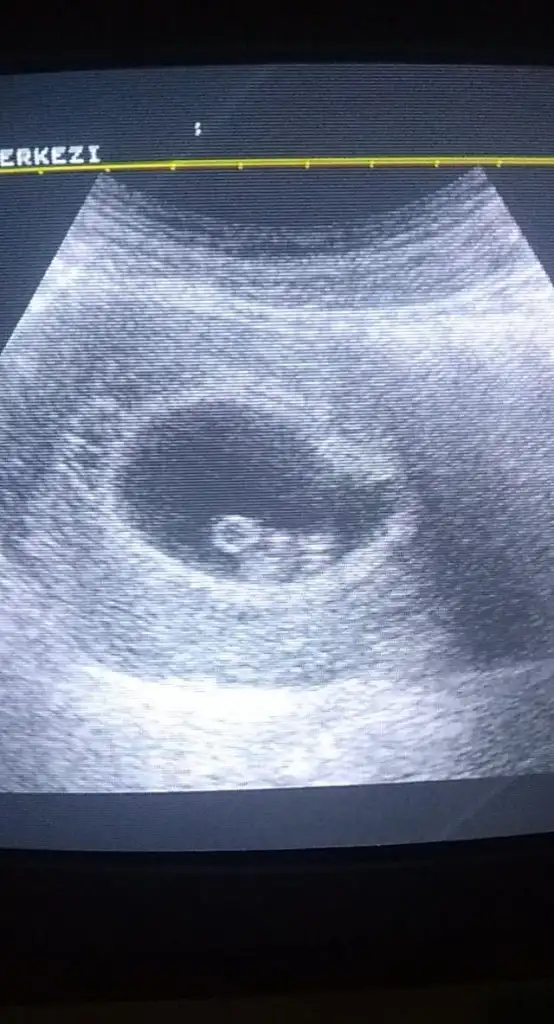

Buna göre kız karından bakıldıysa ama siz nub için 11 yada 12 hafta usg paylaşınBanada tahminde bulunabilir misiniz 8 haftalik

Yani hiç net değil zaten 10 hafta degil 11 yada 12 hafta olmalıbenim bebeğime de bakar mısınız. İlk resim 12 haftalık 2. resim 10 haftalık kızlar hadi yorumunuzu bekliyorum![]()

Kız gibi birde 11 yada 12 hafta usg paylaşırmısınızTeyzeleri bizde tahmin bekliyoruz 13+6 gunlukbizim grupta da tahmin edenler oldu bakalim siz ne diyeceksiniz

10+0 haftalik başka yok yani 11 yada 12 yokKız gibi birde 11 yada 12 hafta usg paylaşırmısınız

10 hafta nub iki tarafa benzer ama sanki kız yönünde gibi 16+ haftadasınız ogrenmedinizmi10+0 haftalik başka yok yani 11 yada 12 yok![]()